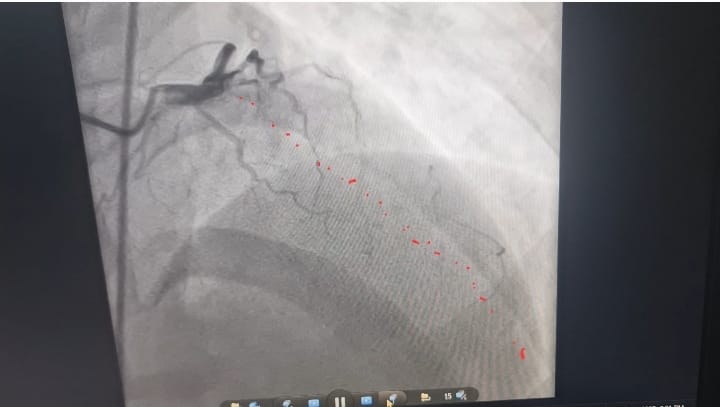

وبعد إجراء رسم القلب والفحوصات الطبية اللازمة، تبين إصابته بجلطة حادة في الشريان الأمامي الرئيسي.

وعلى الفور، قرر الفريق الطبي إجراء قسطرة قلبية عاجلة، حيث تم اكتشاف انسداد تام بالشريان الأمامي، وتم فتحه وتركيب دعامة بنجاح كامل، مما أدى إلى استقرار حالة الشاب وإنقاذ حياته في اللحظات الحرجة.